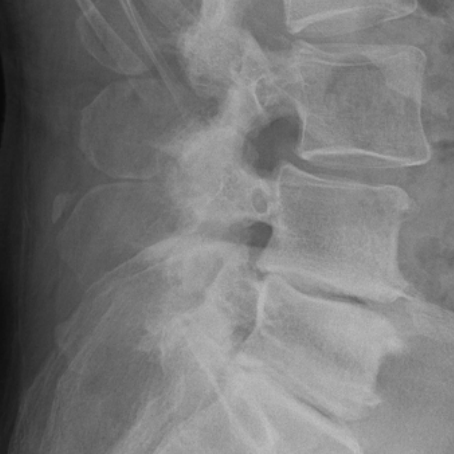

Radiografii din incidenţa anteroposterioară şi laterală ale unui pacient cu spondilolistezis L4-L5 ce a suferit o intervenţie chirurgicală de decompresie şi fuziune intercorporeala posterioară transforaminala cu şuruburi pediculare şi cage PEEK (PLIF)